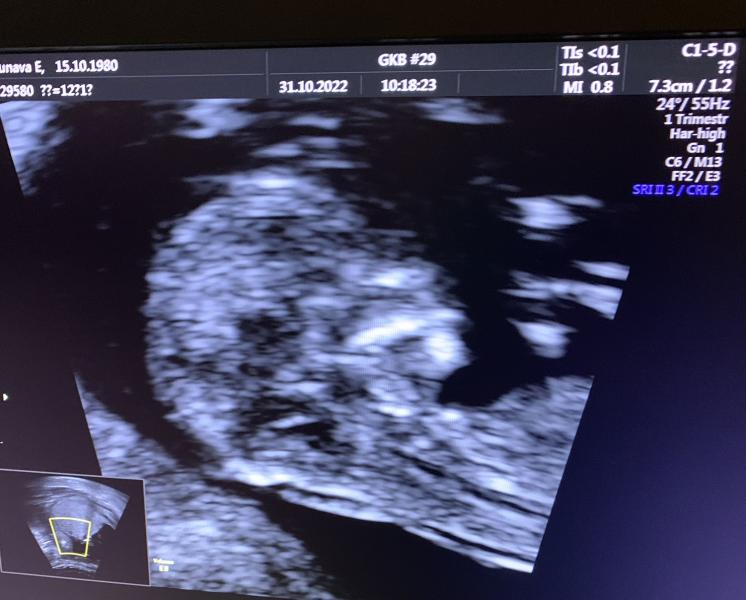

Все у нас хорошо по узи . Врач , которая делала осталась довольна результатом .

Как я поняла они сразу делают по данным узи расчёт рисков и сказала , что все отлично )

Теперь мы опережаем на 3 дня ))

По месячным 12,2 недель

По узи 12,5 недель

Наш Максимка сегодня спал ну узи ))

Твп 1.4